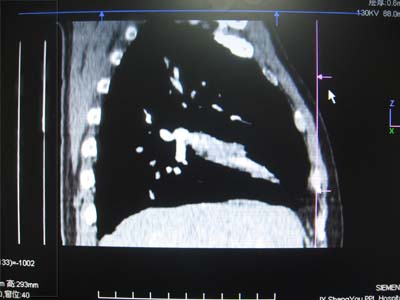

以下是引用zhangzhongshou在2007-5-17 12:08:00的发言:[br]1、右肺中叶不张,建议纤支镜检查。[br]2、左侧胸腔积液,性质待查,建议进一步检查。[br]3、左侧局限性胸膜肥厚。[br][br][本贴已被 zhangzhongshou 于 2007-5-17 12:12:13 修改过]

以下是引用zyx168在2007-5-17 12:44:00的发言:[br]支持[br] 1、右肺中叶不张,建议纤支镜检查。[br] 2、左侧胸腔积液,性质待查,建议进一步检查。[br] 3、左侧局限性胸膜肥厚。 [br]

以下是引用一棵树在2007-5-17 12:11:00的发言:[br]中叶的病变应该谨慎,建议支气管镜检查。